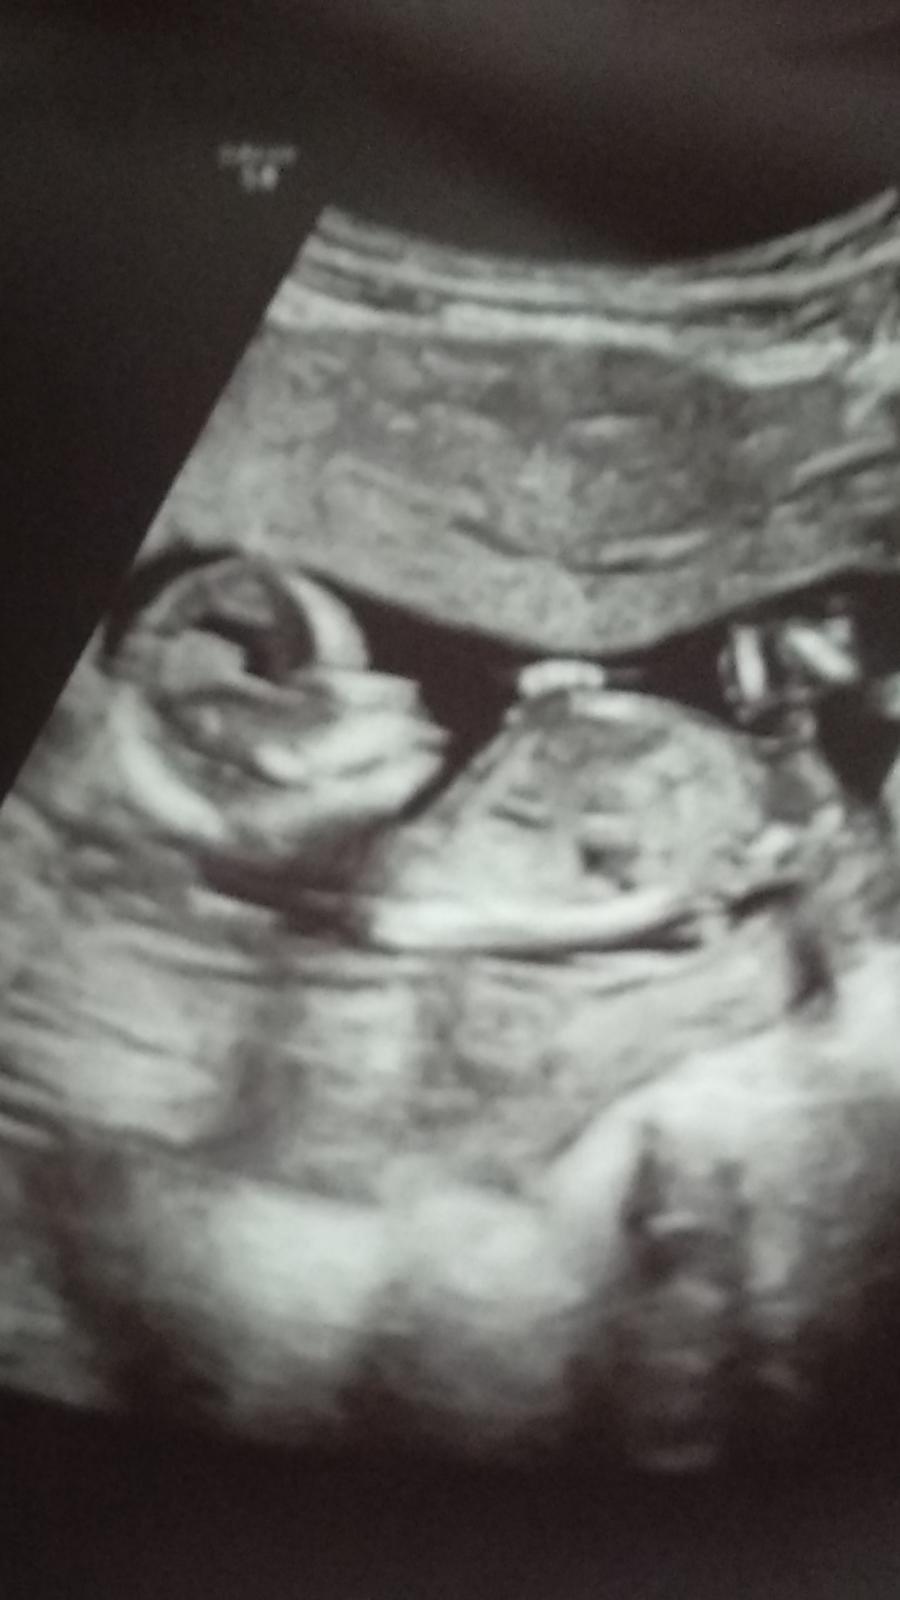

Ultrazvuk. Poznáte pohlaví?

@kesja právě že teprve 13tt ale teď už jsem v 15tt ale stejně mě doktor odflakava že je ještě brzo . U prvního jsem to věděla ve 13tt

Muj tip je holka. V 13tt by byl pytlik az moc veliky. Každopádně je to tip, je jeste moc brzy rikat neco na beton i od dr.

Mě řekli,že až ve 20 tt,že do té doby to nikdy není jistý a nejde poznat úplně přesně 😉

Kluk